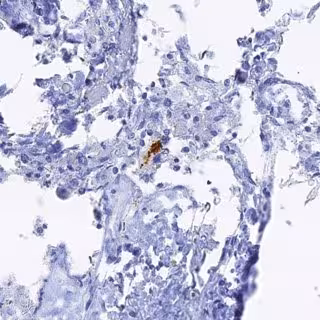

Las infecciones virales por herpes podrían manipular el sistema inmunológico de manera que serían capaces de conducir a enfermedades neurodegenerativas como el Alzheimer, según el estudio del Hospital Monte Sinai de Nueva York (Estados Unidos) y publicado en 'Nature Communications'.

Así, los investigadores han hallado que estos virus manipulan una antigua especie de ARN, originada hace varios millones de años, llamada ARN del satélite humano II (ARN HSATII). El ARN HSATII normalmente está inactivo, pero los virus por herpes y las células cancerosas, fundamentalmente, han aprendido a activarlo y utilizan este ARN para manipular su entorno con el fin de ir creciendo hasta invadir el cuerpo.

El estudio brinda también información adicional sobre cómo los virus del herpes podrían jugar un papel en el desarrollo de colitis y enfermedades neurodegenerativas como el Alzheimer. Este constituiría el primer paso hacia el desarrollo de herramientas de diagnóstico que "busquen estos tipos de ARN en pacientes con cáncer y herpes y que utilicen los ARN antiguos como objetivos para medicamentos en el futuro", explica Greenbaum.